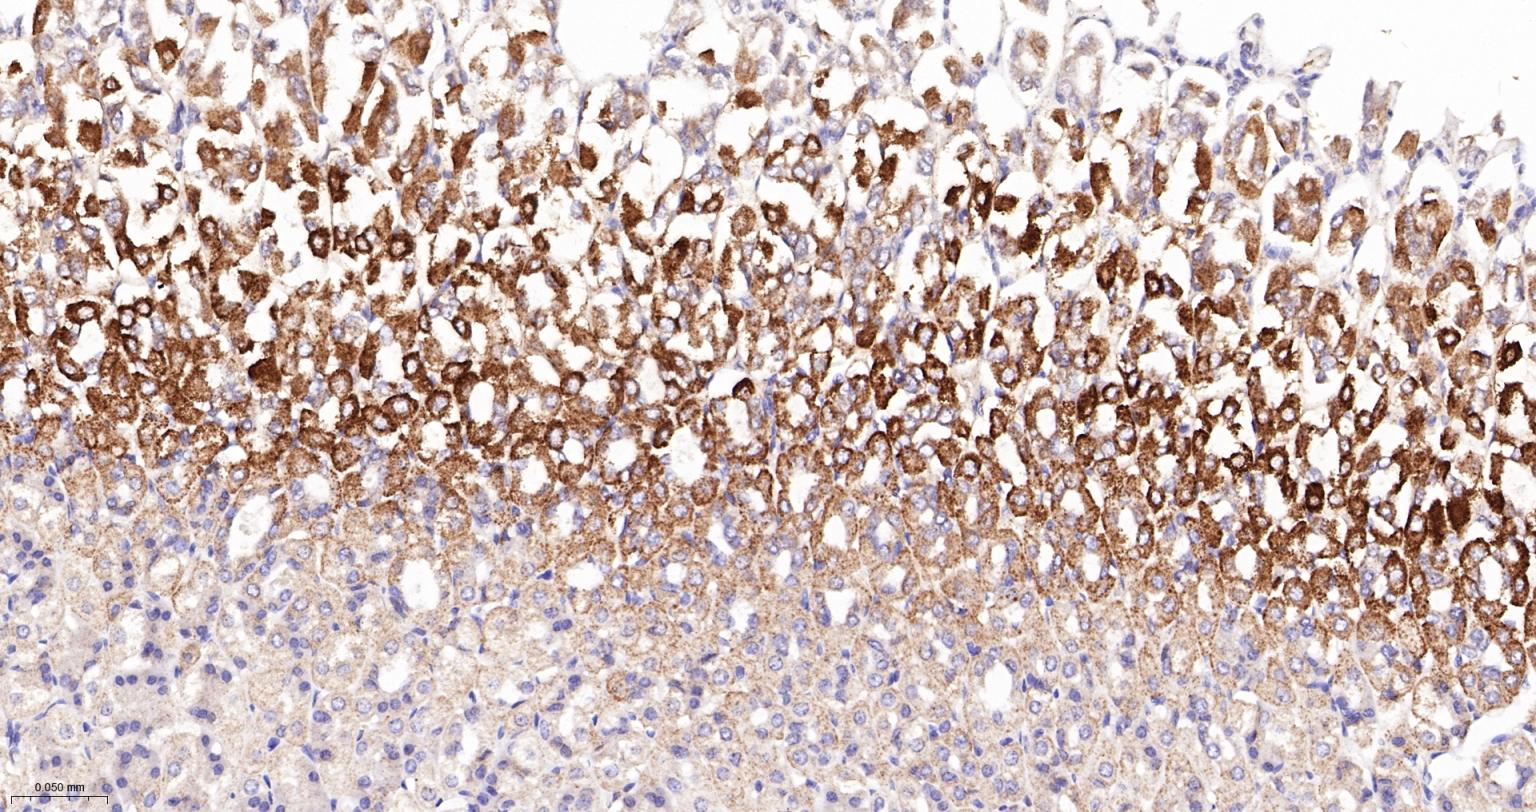

Paraformaldehyde-fixed, paraffin embedded Human Cerebrum; Antigen retrieval by boiling in sodium citrate buffer (pH6.0) for 15 min; The section was incubated with NDUFS2 Monoclonal Antibody, Unconjugated (bsm-62748R) at 1:200 overnight at 4°C, followed by conjugation to the bs-0295G-HRP and DAB (C-0010) staining.

Paraformaldehyde-fixed, paraffin embedded Rat Cerebrum; Antigen retrieval by boiling in sodium citrate buffer (pH6.0) for 15 min; The section was incubated with NDUFS2 Monoclonal Antibody, Unconjugated (bsm-62748R) at 1:200 overnight at 4°C, followed by conjugation to the bs-0295G-HRP and DAB (C-0010) staining.

Paraformaldehyde-fixed, paraffin embedded Mouse Cerebrum; Antigen retrieval by boiling in sodium citrate buffer (pH6.0) for 15 min; The section was incubated with NDUFS2 Monoclonal Antibody, Unconjugated (bsm-62748R) at 1:200 overnight at 4°C, followed by conjugation to the bs-0295G-HRP and DAB (C-0010) staining.